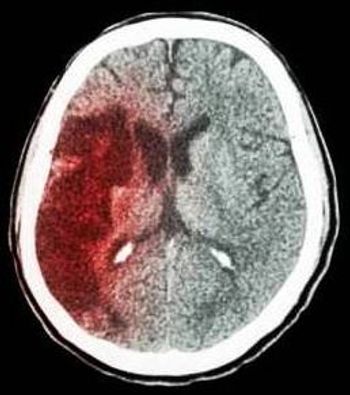

The risk for major bleeding and GI hemorrhage in patients taking dabigatran was greater than in those taking warfarin; warfarin, however, was associated with a greater risk of intracranial hemorrhage.